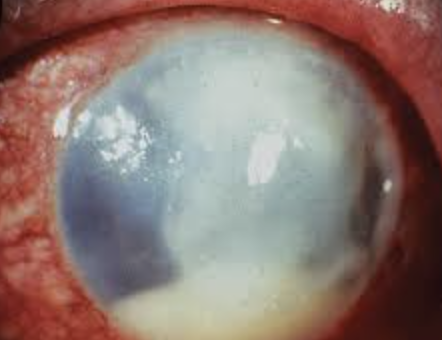

Descemetocele: serious condition where Descemet membrane (a layer of the cornea) protrudes or bulges forward due to thinning of the corneal stroma, often caused by a corneal ulcer, and requires prompt intervention to prevent perforation

Causes of corneal ulcer: Microbial keratitis, neurotrophic keratopathy, dry eye disorders, and corneal inflammation (sterile ulcer) associated with immune-mediated disorders can lead to corneal ulcers

Plan: Refer for penetrating keratoplasty

Corneal opacification: occurs when the cornea's transparency is lost, often due to scarring or edema, disrupting the regular arrangement of collagen fibrils and leading to light scattering/opacification

Corneal hydrops, a serious complication of keratoconus, occurs when a tear in Descemet's membrane allows fluid from the eye to leak into the corneal stroma, causing swelling and clouding

Hydrops: Occurs due to Descemet layer damage resulting in edema. Complication of pellucid and keratoconus and trauma/eye surgery. Can lead to scarring and reduced vision. May need corneal transplant if severe. Most resolve within a few months with proper treatment at proper times.

Plan: Descemet heals in 3 months. During the 3 months, need to reduce risk of scarring by using Muro 5% BID, brimonidine 0.1% BID, steroid if neo and eye shield.

Bullous Keratopathy: blister-like swelling (bullae) of the cornea due to corneal endothelial dysfunction, leading to fluid accumulation and vision impairment

Objective: Corneal edema, bullae, Descemet folds, sub-epi haze, corneal neo, gutatta. Might even be cystoid macular edema

Workup: Stain, IOP, mac oct (RO CME)

Plan: Muro 128 ung and gtt. Timolol to reduce IOP (avoid prostglandin)

Plan if ruptured: treat epithelial defect with moxifloxacin, BCL, cyclo

1-3 days for bullae. 7 days initially then 1-6 months

Escalation: PTK, amniotic membrane, DSEK